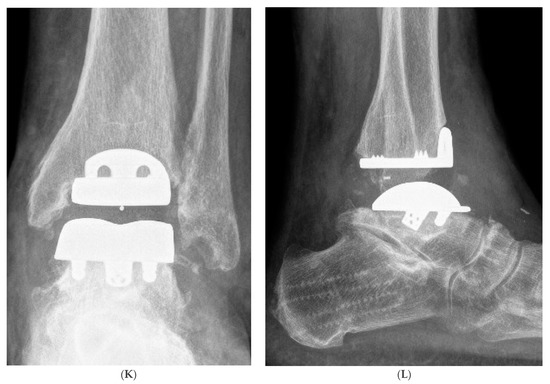

Hybrid Total Ankle Arthroplasty (H-TAA). This figure represents Case Nr. 7 of the cohort (see Table 1, Table 2 and Table 3). (A–D): Preoperative X-rays and CT-scans depicting the cyst under the talar component of the Hintegra TAA. (E,F): Intraoperative pictures showing the inlay breakage with poor bone osteointegration in the backside of the talar component of the Hintegra TAA. (G): Talar cyst with stable tibial Hintegra component. (H): Performance of a flatcut of the talus and bone grafting of the talar cyst with iliac crest autologous spongiosa. (I): Flatcut Talar Component of the VANTAGE TAA, which is implanted on the reconstructed talus. (J): H-TAA: Tibial component Hintegra TAA with new Flatcut Talus and Inlay of VANTAGE TAA. (K,L): Postoperative X-rays with H-TAA, good talar bone reconstruction, and good integration of the Flatcut Talus of VANTAGE TAA.

The postoperative H-TAA X-rays at follow-up showed a good talar bone reconstruction and good osteointegration of the new VANTAGE talar component in all cases (no radiolucency, no loosening). The existing tibial components were unchanged and showed no loosening. No complications or reoperations for any of the included patients were noticed.